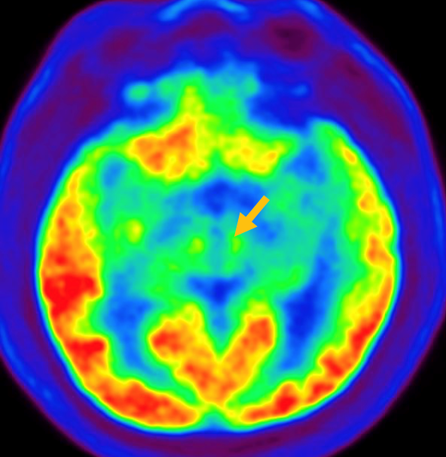

루이소체 치매는 파킨슨 증상 발생 초기나 그 이전부터 빠르게 진행되는 인지 기능 저하가 동반되는 질병입니다. 퇴행성 치매의 원인 중 두 번째로 많습니다. 반복되는 환시 증상과 인지, 의식 및 집중력의 변동이 특징적으로 나타납니다. 뇌 자기공명영상(MRI)에서 전반적인 대뇌 위축이 나타나며, 알츠하이머병에 비해 상대적으로 후두엽, 내측 측두엽이 보존되는 모습이 관찰됩니다. 뇌포도당 양전자 단층촬영(PET)을 시행하면 쐐기소엽(cuneus) 및 쐐기앞소엽(precuneus)의 대사가 감소한 상태가 확인됩니다. 그러나 뒤띠이랑(posterior cingulate gyrus)은 상대적으로 보존된 모습을 볼 수 있습니다.

[루이소체치매 환자의 뇌포도당 양전자 단층촬영에서 확인되는 비대칭적인 대사 기능 저하]